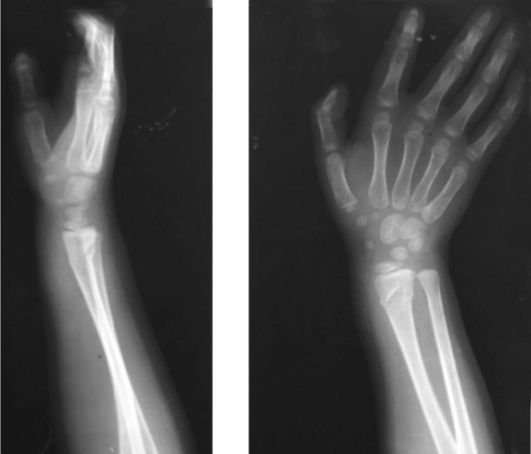

Самая частая локализация травматического эпифизиолиза у детей©

+В дистальном отделе лучевой кости©

Какой вид травматического повреждения определяется на рентгенограмме© Вывих кисти© Вывих предплечья© Эпифизиолиз© +поднадкостничный перелом© Неполный перелом